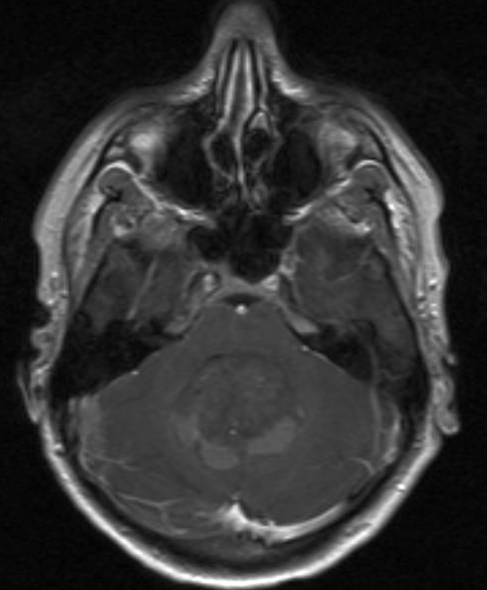

MR-scanning viser et medulloblastom i 2 vinkler (axialt, sagittalt)

Gengivet med tilladelse fra Radiologisk afdeling, Universitetssygehuset Nord-Norge